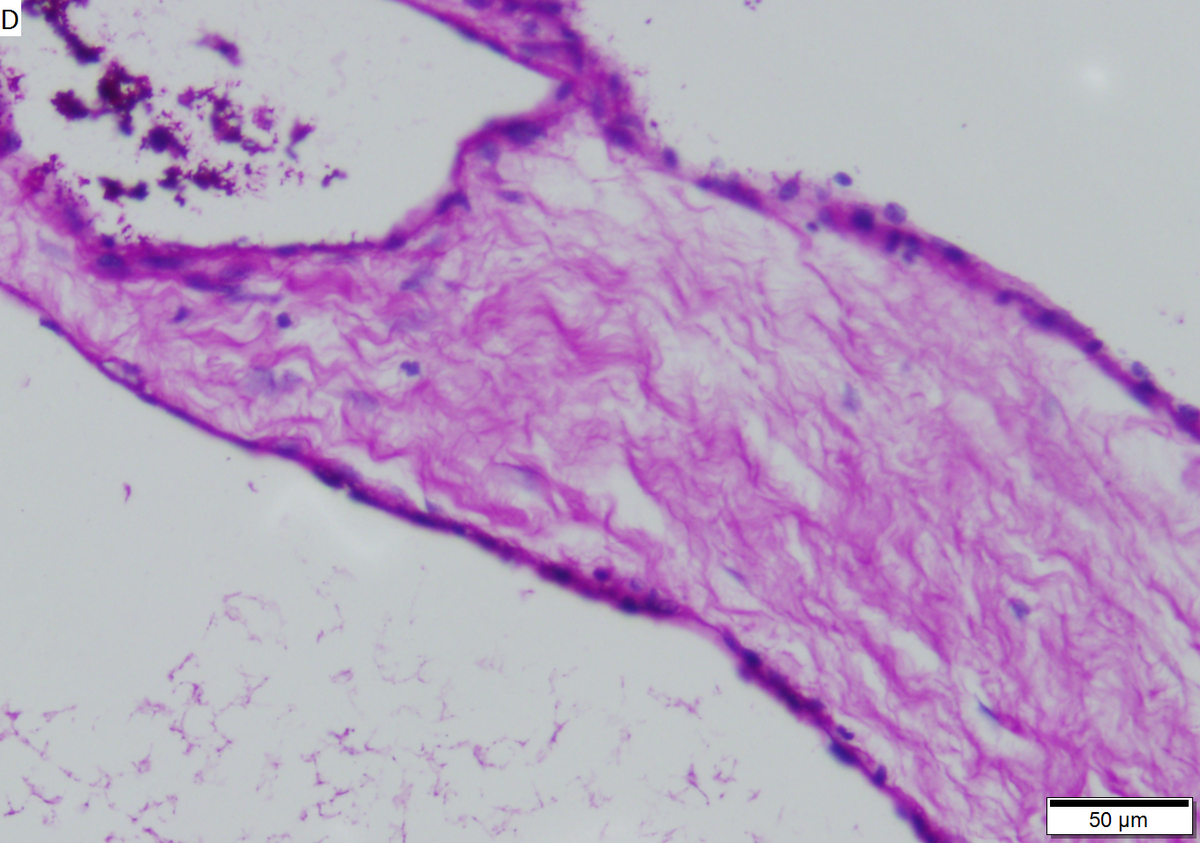

Microcystic serous cystadenoma of pancreas in a 62 year old woman. A. The tumor showed a central scar with multiple minute cysts; slight pressure yielded clear fluid. B. The mass comprises microcysts numberless. C. Cysts bear single cell linings with bland, amitotic nuclei. D. PAS without diastase shows positive cytoplasmic material. E. PAS with diastase shows the cytoplasmic material has been digested away. F. Keratin shows positive staining lining cells.

LM small cystic spaces lined by cytologically bland cuboidal cells

• Cystic spaces lined by cuboidal cells.

• Glycogen rich.